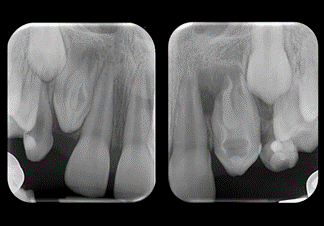

۳. نقش رادیوگرافی و CBCT

رادیوگرافی معمولی (Periapical X-ray): ابزار اصلی و اولیه است ولی دو بعدی بودن آن محدودیت دارد.

CBCT:

o تشخیص ضایعات اپیکال کوچک یا مخفی

o بررسی شکستگی‌های عمودی ریشه

o شناسایی ریشه‌های اضافی و کانال‌های غیرمعمول

o کمک به برنامه‌ریزی در درمان‌های مجدد و جراحی اندودنتیک

مطالعات نشان داده‌اند که CBCT نسبت به رادیوگرافی معمولی حساسیت بالاتری در شناسایی ضایعات آپیکال دارد (Patel et al., IEJ 2009).